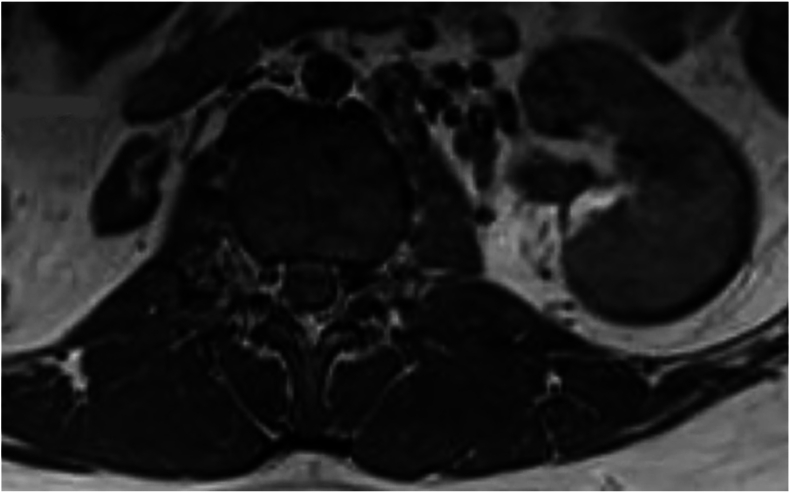

Results: The average age of the 1409 patients was 15.5 years (95% CI: 15.4, 15.6). Back pain (90.1%) was the most common reason for lumbar MRI. Thirty-five UFs were found in 33 patients (2.3%): 19 were spinal cord-related, 15 were peritoneal-related, and one was vascular. Eight peritoneal findings involved the kidneys: two atrophy, two hypoplasia, two renal cysts, one pelvic kidney, and one hydronephrosis. Five patients had a syrinx, and two had spine tumors. Out of 33 patients with UFs, 11 required a change in treatment plan (33.3%). Back pain was not associated with an increased risk of UF. Patients with an UF on MRI had 2.60 times higher odds of experiencing a change in treatment plan.

Abstract Image